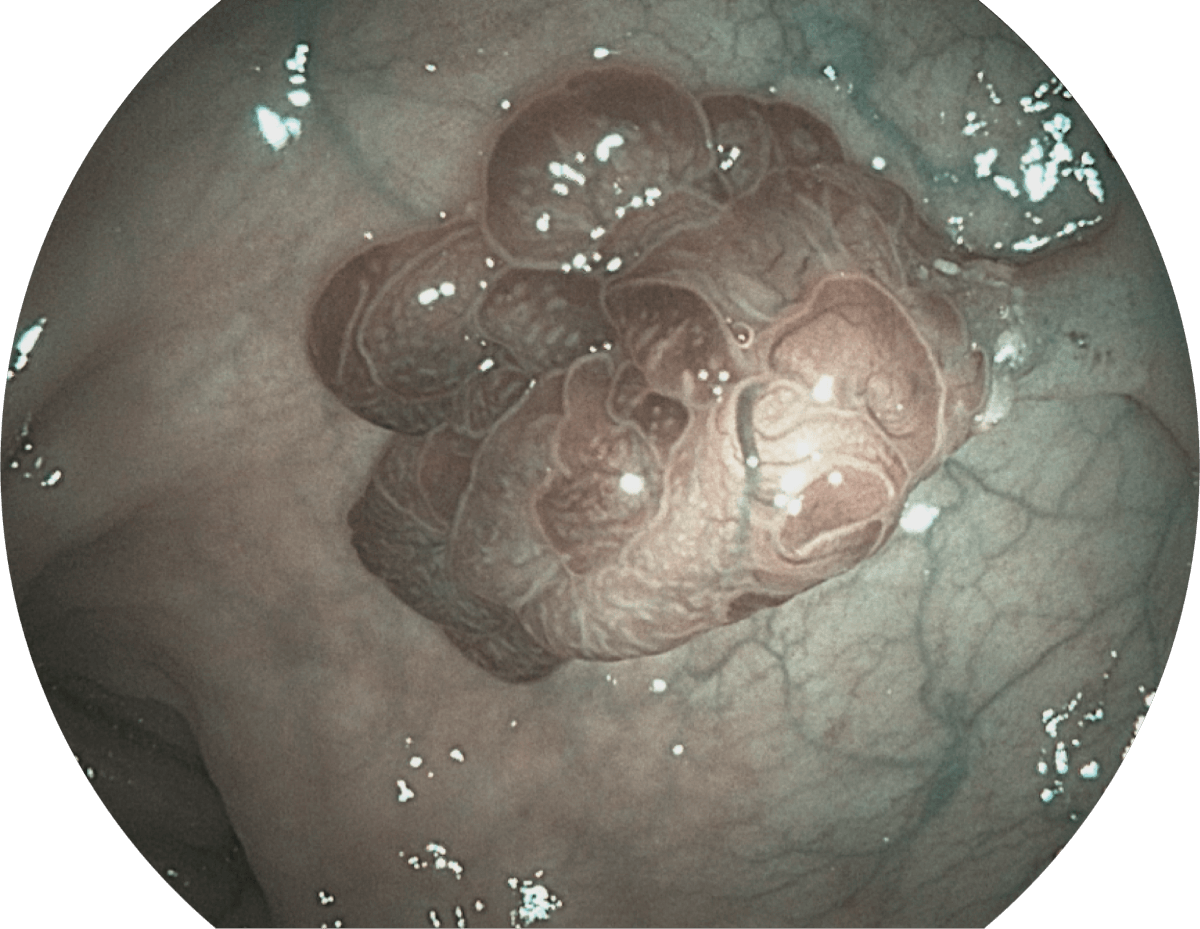

具有聚谱成像技术(SFI)及光电复合染色成像技术(VIST),可完美呈现粘膜细节及病变特征。

WL

SFI

VIST

图像增强的同时,压低噪点,凸显微小病变轮廓,提高检出率。